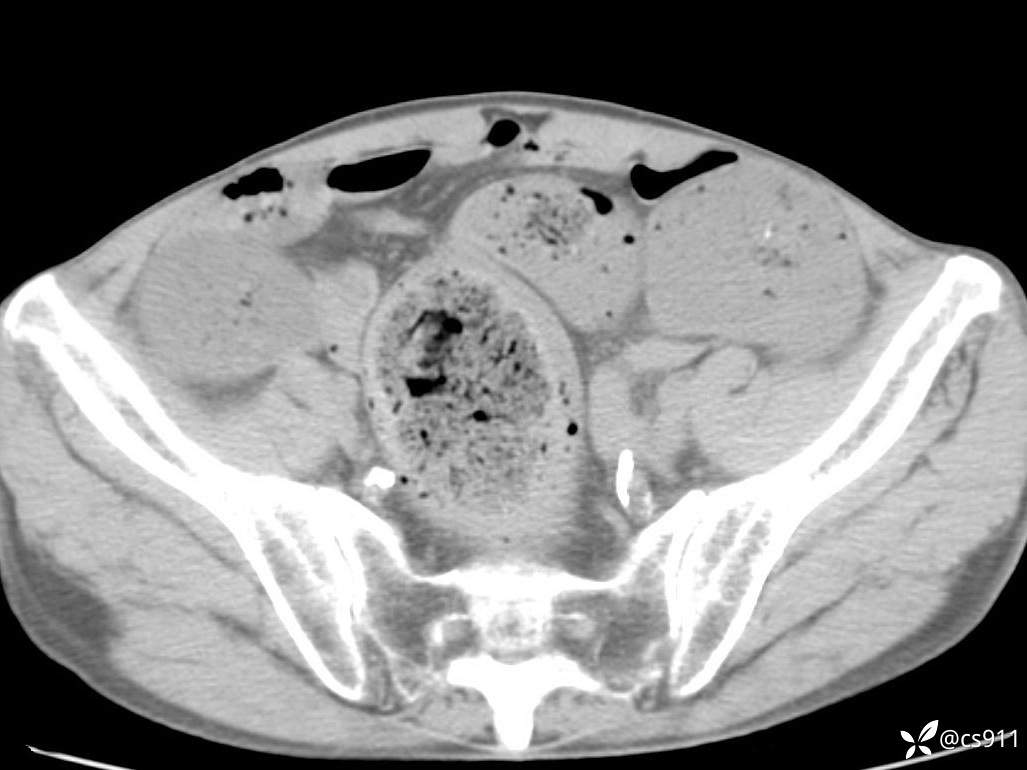

急腹症之急诊CT,原因?答案公布

男,77岁,腹痛、腹胀伴恶心呕吐1天。呕吐胃内容物,非喷射性呕吐,有咖啡色样胃内容物,诉有胃穿孔病史。查体:全腹平,下腹部压痛,全腹无反跳痛,叩诊呈浊音,移动性浊音阴性,肠鸣音减弱,1-2次/分。肛检:直肠未扪及明显肿物,可触及大量粪块。

血淀粉酶(AMY) HH 1859 U/L 35-135